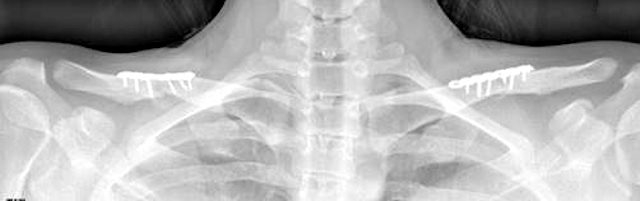

Clavicle osteotomies for Shoulder Width Reduction postop x-ray Dr Barry Eppley Indianapolis

The Surgical Technique of Clavicular Osteotomies in Shoulder Width Reduction

Shoulder width reduction is done by shortening the length of the...